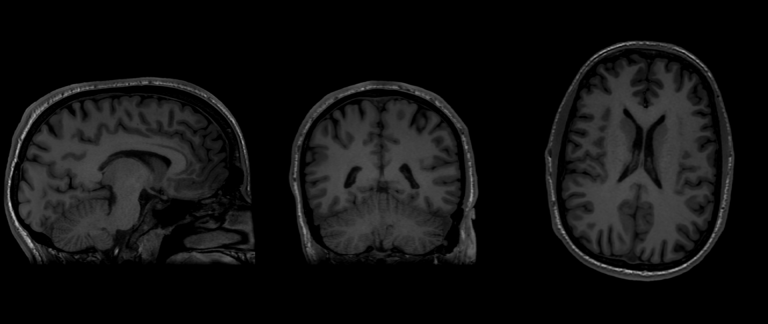

Imaging Capabilities With our brand-new General Electric 3.0 Tesla MRI Scanner, the suite is capable of performing a host of imaging analysis including the following: Site Menu Menu Icon of three lines stacked on top of eachother Sidebar Menu Chev Down Icon of hollow arrow pointing down Arrow Left Icon of arrow pointing left Neurotechnology Suite Chev Up Icon of hollow arrow pointing up Imaging Capabilities CONTACT Location: 50 Prescott Street (Gateway Park II) practicepoint@wpi.edu LinkedIn Icon of LinkedIn Logo